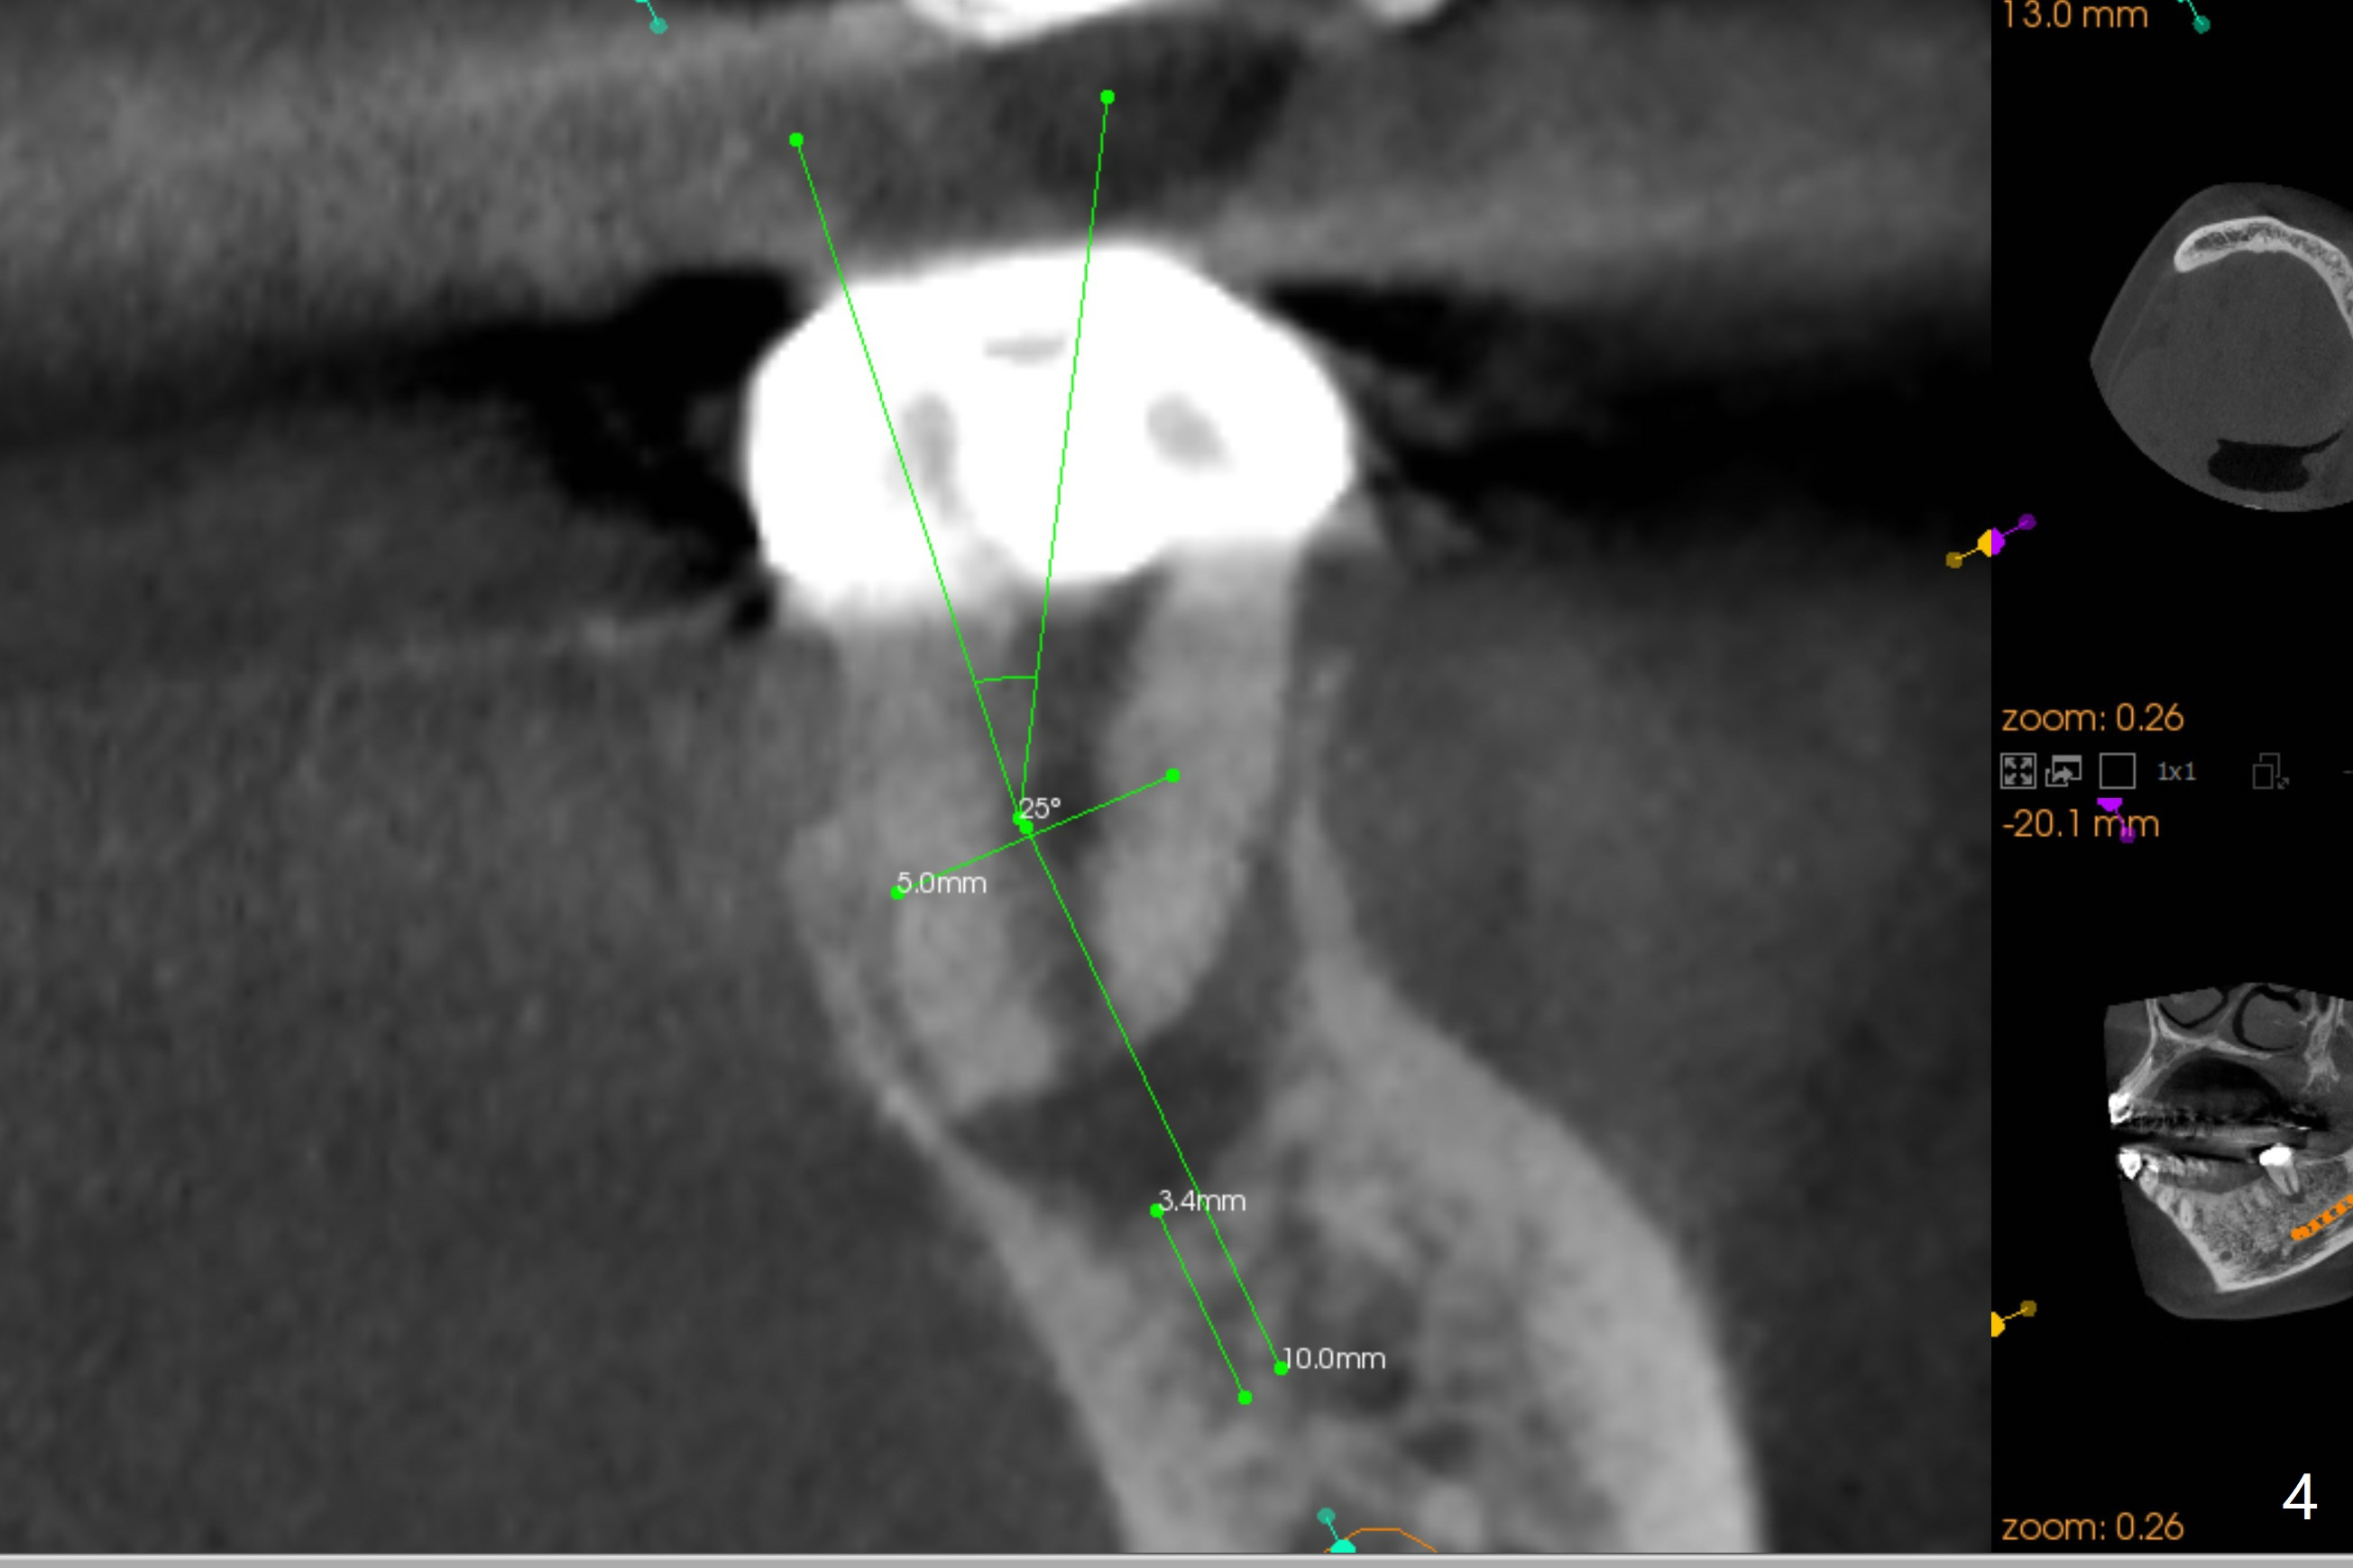

A 54-year-old woman will return for #18 extraction and implant 1 or 2 years post implants at #19 and #30. In fact the tooth has had incomplete RCT with PARL. Reanalysis of CT taken on 02/02/2017 (before RCT) shows that RCT retreatment should not be too difficult (Fig.1,2). If the treatment turns out to be not successful, a 5x10 mm immediate implant will be done with a possible 25 degree angled abutment (Fig.3,4).